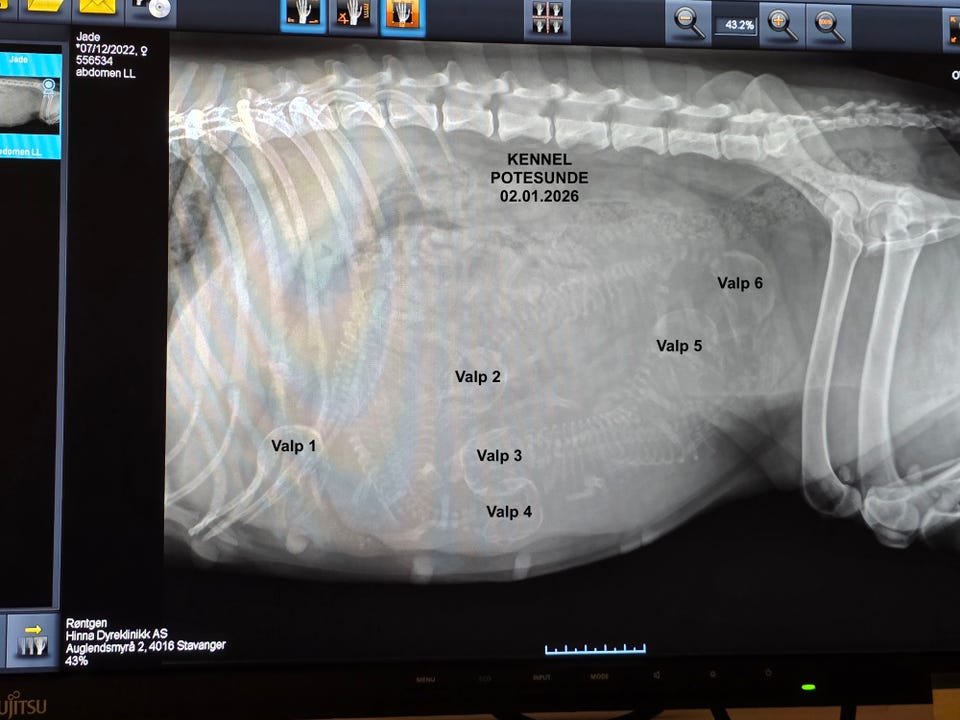

Mor: Bernegården´s Jade NO30235/23